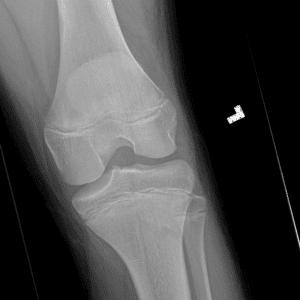

Pediatric Radiographs